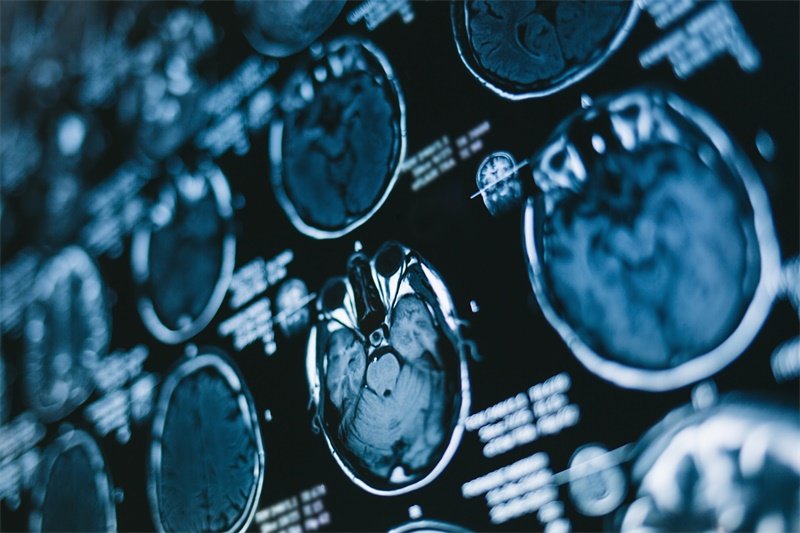

大脑镰旁占位病变是指发生在大脑镰旁区域的各种病变,这一部位是大脑半球之间的一个解剖结构。该区域的病变可以引起一系列的神经症状,影响患者的生活质量。大脑镰旁是指左右大脑半球之间的一片脑组织区域,它在维持大脑的正常功能中扮演着重要角色。

肿瘤是导致大脑镰旁占位病变的主要原因之一。肿瘤可以是良性或恶性,来自大脑的原发肿瘤或外部转移的癌症。它们可能对周围组织造成压迫,从而影响脑功能。

如脑膜瘤是常见的良性肿瘤,通常发生在大脑的脑膜上,并可能扩展到镰旁区域。恶性肿瘤,如转移性脑瘤,则可能起源于全身的其他癌症,如肺癌、乳腺癌等,当这些癌细胞达到大脑时,会在镰旁区域形成占位性病变。